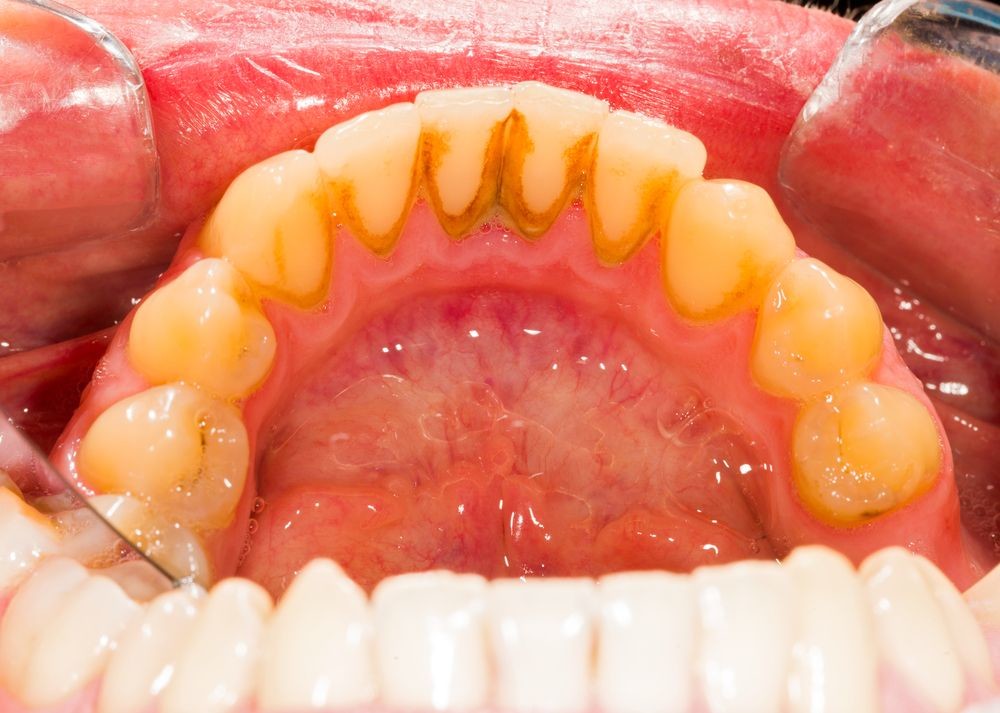

Oral biofilms, a concern for all dental professionals

Biofilms are a collective of one or more types of microorganisms that can grow on many different surfaces. Microorganisms that form biofilms include bacteria, fungi and protists.

One common example of a biofilm dental plaque, a slimy buildup of bacteria that forms on the surfaces of teeth. Pond scum is another example. Biofilms have been found growing on minerals and metals. They have been found underwater, underground and above the ground. They can grow on plant tissues and animal tissues, and on implanted medical devices such as catheters and pacemakers.

Role of oral biofilm in the aetiology of disease:

Oral biofilm is medically important because it has broad implications for maintaining not only oral health but also systemic health. It is estimated that biofilms account for over 80% of microbial infections in the body. Research has undoubtedly shown that biofilm-dependent infections, including oral diseases such as caries, and periodontal and endodontic disease, thus pose major public health and cost concerns globally.

Periodontal disease, in particular, is considered one of the most prevalent diseases worldwide, affecting up to 50% of the world’s adult population, according to FDI World Dental Federation. Previous research has established connections between periodontal disease and preterm births, low birthweight, diabetes, and risk factors associated with cardiovascular disease and stroke. Globally, periodontitis is responsible for an estimated US$54 billion per year in lost productivity and a major portion of the US$442 billion spent annually on oral disease, according to the European Federation of Periodontology.

Control of oral biofilm:

Owing to the vast implications of oral biofilm for dental and general health, its effective control represents a major challenge. There is no question that the formation and maturation of oral biofilm need to be tackled by dental professionals across all specialties in all countries worldwide.

“The backbone of any therapeutic and preventive approach is the disruption of the intra-oral biofilm. An example of technologies that have been successfully demonstrated to aid supra- and subgingival instrumentation are air polishing devices with low-abrasive powders that can disrupt the biofilm on all intra-oral surfaces, including mucous membranes and difficult-to-reach subgingival areas, without harming the hard tissue and the even more vulnerable soft tissue,” Beikler explained. “Their effects can be augmented by antimicrobial and immune- and microbiome-modulating strategies. Regarding the latter, probiotics offer an interesting and promising alternative to the use of unspecific antimicrobial agents like chlorhexidine or phenolic compounds. However, additional research, that is, appropriately designed and well-structured multicentre clinical trials, is critically needed to fully appraise their therapeutic effects,” he continued.

Another major challenge that needs to be taken into consideration in this respect is that trying to eliminate a specific pathogen using antimicrobial agents may disturb the sensitive microbial ecology and eventually induce microbial dysbiosis of the oral cavity.

Education on oral biofilm:

Until the early 1990s, dentists confined their treatment for combating oral plaque to removing calculus twice a year because there was only limited understanding of biofilm. Over the past decades, research on and improved knowledge about the parameters that determine the development of oral disease have spurred the development of new preventive strategies. For instance, piezoceramic instruments and low-abrasion powders have made professional biofilm management safer, minimally invasive and more comfortable for both the patient and the dental practitioner. Moreover, the launch and further development of AIRFLOW devices by EMS fundamentally changed biofilm management and eventually resulted in the development of Guided Biofilm Therapy, an innovative concept for contemporary prophylaxis.

As research and development of new technologies and therapies continues to progress, so too does knowledge in the dental professional community need to advance for effective integration of these developments into everyday practice for the well-being of the patient.

“As biofilms can be found on all oral surfaces, it is clear that all dental disciplines, ranging from dental hygienists to orthodontists, are highly affected by oral biofilm and its sequelae,” highlighted Beikler. “Unfortunately, prevention is sometimes still considered to be toothbrushing augmented by some kind of professional tooth cleaning. However, the whole oral cavity should be the therapeutic focus of a systematic preventive approach.”